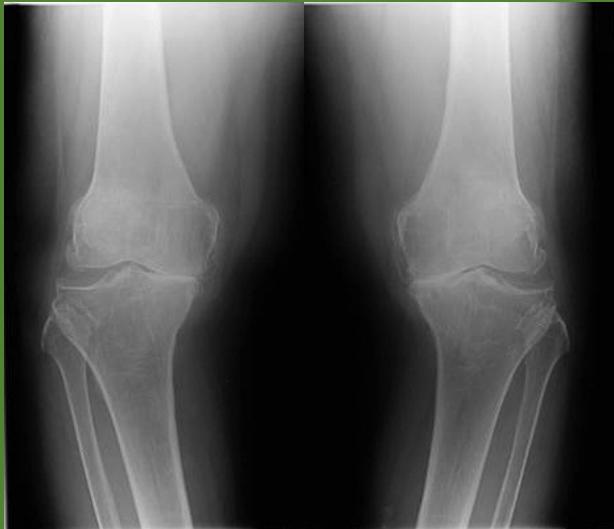

Case 1: Lady with Chronic Knee Pain

- 54 year old lady, presented to the clinic with pain in both knees for 3 years

Imaging Studies

- Standard Radiographs:

- Both knees AP standing views (weight-bearing)

- Lateral views of both knees

- Skyline view (patellofemoral assessment)